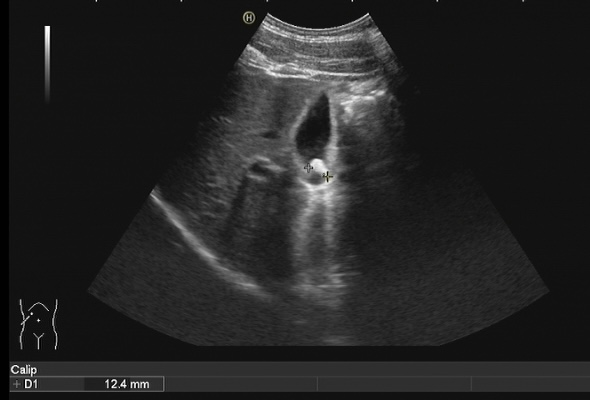

胆结石诊断方式很多,包括彩超、CT、核磁共振、胆管造影等方式都可以对胆道结石进行诊断,但是彩超具有无创、无痛、无辐射、廉价、快速、可重复性强等优点,在临床上被广泛应用作为胆结石的首选诊断方式。注意做肝胆彩超检查必须要空腹,才能准确检查出胆道结石哦!

胆囊结石超声图像 | |